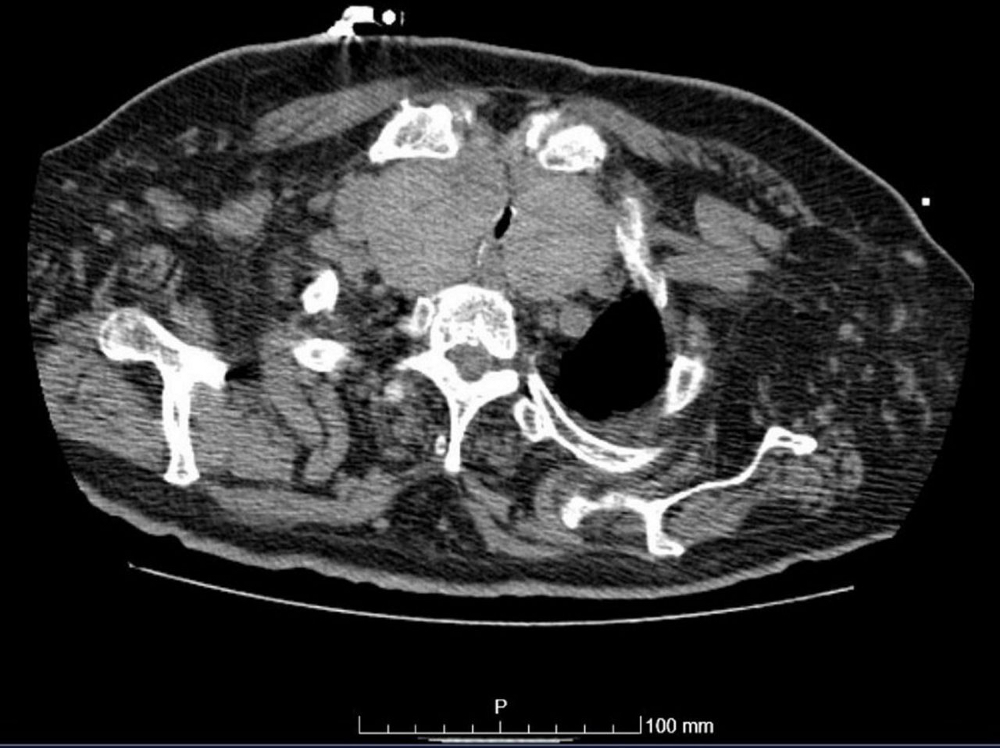

CT neck (non-contrast)

Test

Occasionally indicated for signs or symptoms of neck compression, or as part of pre-operative evaluation before thyroid surgery.[Figure caption and citation for the preceding image starts]: Chest CT showing marked enlargement of the thyroid gland with an extensive intrathoracic component causing trachea compressionDias T et al. Acute airway obstruction due to benign multinodular goitre. BMJ Case Reports. 2019;12:e228095; used with permission [Citation ends].

Result

may delineate large goitre